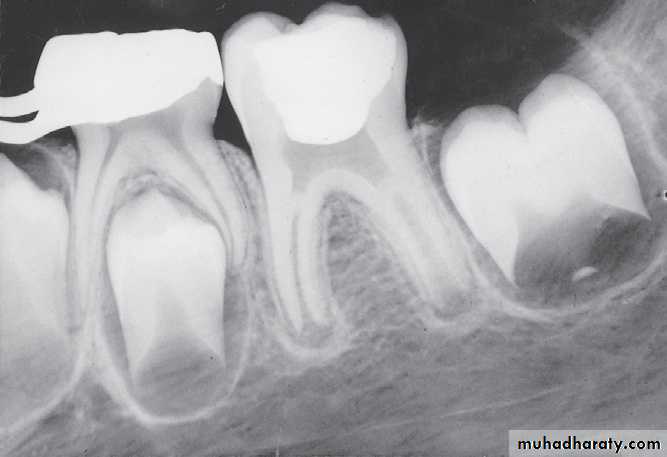

Internal resorption after calcium hydroxide pulpotomy in a primary tooth

Deep caries in the first primary molar and due to that caries resorption in the bifurcation areaDeep caries in the mandibular second primary molar

Periapical radiographs